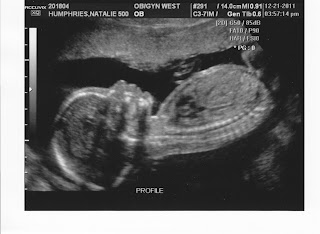

So it looks like Brad and Maddie are going to have a little sister this Spring!! We went in for our 21 week ultrasound this week and were thrilled with all of the results.  We have a healthy little girl growing and developing just as she should be.  :) Our due date was right on, so we are still looking at May 3rd 2012 for the arrival of our newest family member.  We are very excited that Maddie and her sister will be so close in age and be able to have such a special relationship growing up.  If this one comes early like Maddie did, they will technically be "Irish Twins".  Brad will have his work cut out watching out for two little sisters, but he sounds very excited and up for the challenge.  Here are a few of the ultrasound pictures that we were able to take home.

The ultrasound tech had NO DOUBT she was a little girl.  :)